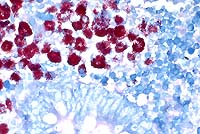

The macrophages throughout the intestinal lesions are distended

with mycobacteria, confirmed by Ziehl Nielsen stains, but apparent

as fine basophilic cytoplasmic stippling in H&E-stained sections.

The intestinal macrophage is the target cell for infection by M. a. paratuberculosis. After the organisms are ingested, they undergo endocytosis by intestinal M cells. Intact and degraded mycobacteria are transported in vacuoles across the M cells to macrophages in subepithelial areas. Specific macrophage receptors for this organism have not been identified, although other mycobacteria use complement receptor types 1 and 3 on macrophages. After uptake by macrophages, the bacteria often resist the degradative and killing mechanisms of the macrophage via sulphatide production, which prevents phagosome-lysosome fusion, escape from the phagosome into the cytoplasm, glycolipid-mediated inhibition of nitric oxide production, and inhibition of the respiratory burst and oxidative killing mechanisms by superoxide dismutase and glycolipid production.